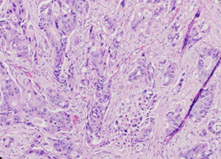

Σχήμα 2 . Μεγαλοκυτταρικό νευροενδοκρινικό καρκίνωμα, θετικό για χρωμογρανίνη Α, και μέτρια διαφοροποιημένο αδενοκαρκίνωμα σε εικόνα σύγκρουσης.